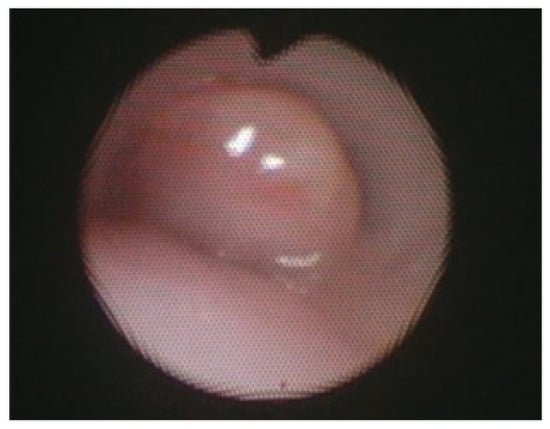

A 30-year-old previously healthy man presented with fever and headache. HIV tests yielded negative results. Cerebrospinal fluid (CSF) analysis revealed pleocytosis (619/µL), elevated protein (210.3 mg/dL) and adenosine deaminase levels, and decreased glucose levels. A positive CSF culture for tuberculosis confirmed the patient [...] Read more.

A 30-year-old previously healthy man presented with fever and headache. HIV tests yielded negative results. Cerebrospinal fluid (CSF) analysis revealed pleocytosis (619/µL), elevated protein (210.3 mg/dL) and adenosine deaminase levels, and decreased glucose levels. A positive CSF culture for tuberculosis confirmed the patient had tuberculous meningitis (TBM). He was treated with methylprednisolone, isoniazid, rifampicin, pyrazinamide, and ethambutol (all highly sensitive). His compliance with medication was good. After six weeks of treatment, he was discharged in stable condition. Eight weeks after onset, he was readmitted with vertigo and right deafness. CSF examination showed worsened pleocytosis (819/µL) and protein levels (4296.1 mg/dL). Contrast-enhanced MRI revealed enhancement of meninges in the brainstem and spinal cord as well as the right vestibulocochlear nerve. No brain abscesses were observed. Based on these findings, a paradoxical reaction (PR) with vestibulocochlear neuritis following antituberculous therapy initiation was suspected. He received oral prednisolone, leading to rapid resolution of vestibulocochlear symptoms within two days. Although cranial nerve enhancement due to PR has been mentioned in the literature, specific imaging demonstrating it is scarce. This case highlights PR as a cause of cranial neuropathy in TBM and provides clear radiological evidence of direct inflammatory spread to the vestibulocochlear nerve, bridging a gap in the current literature. Full article

Figure 1